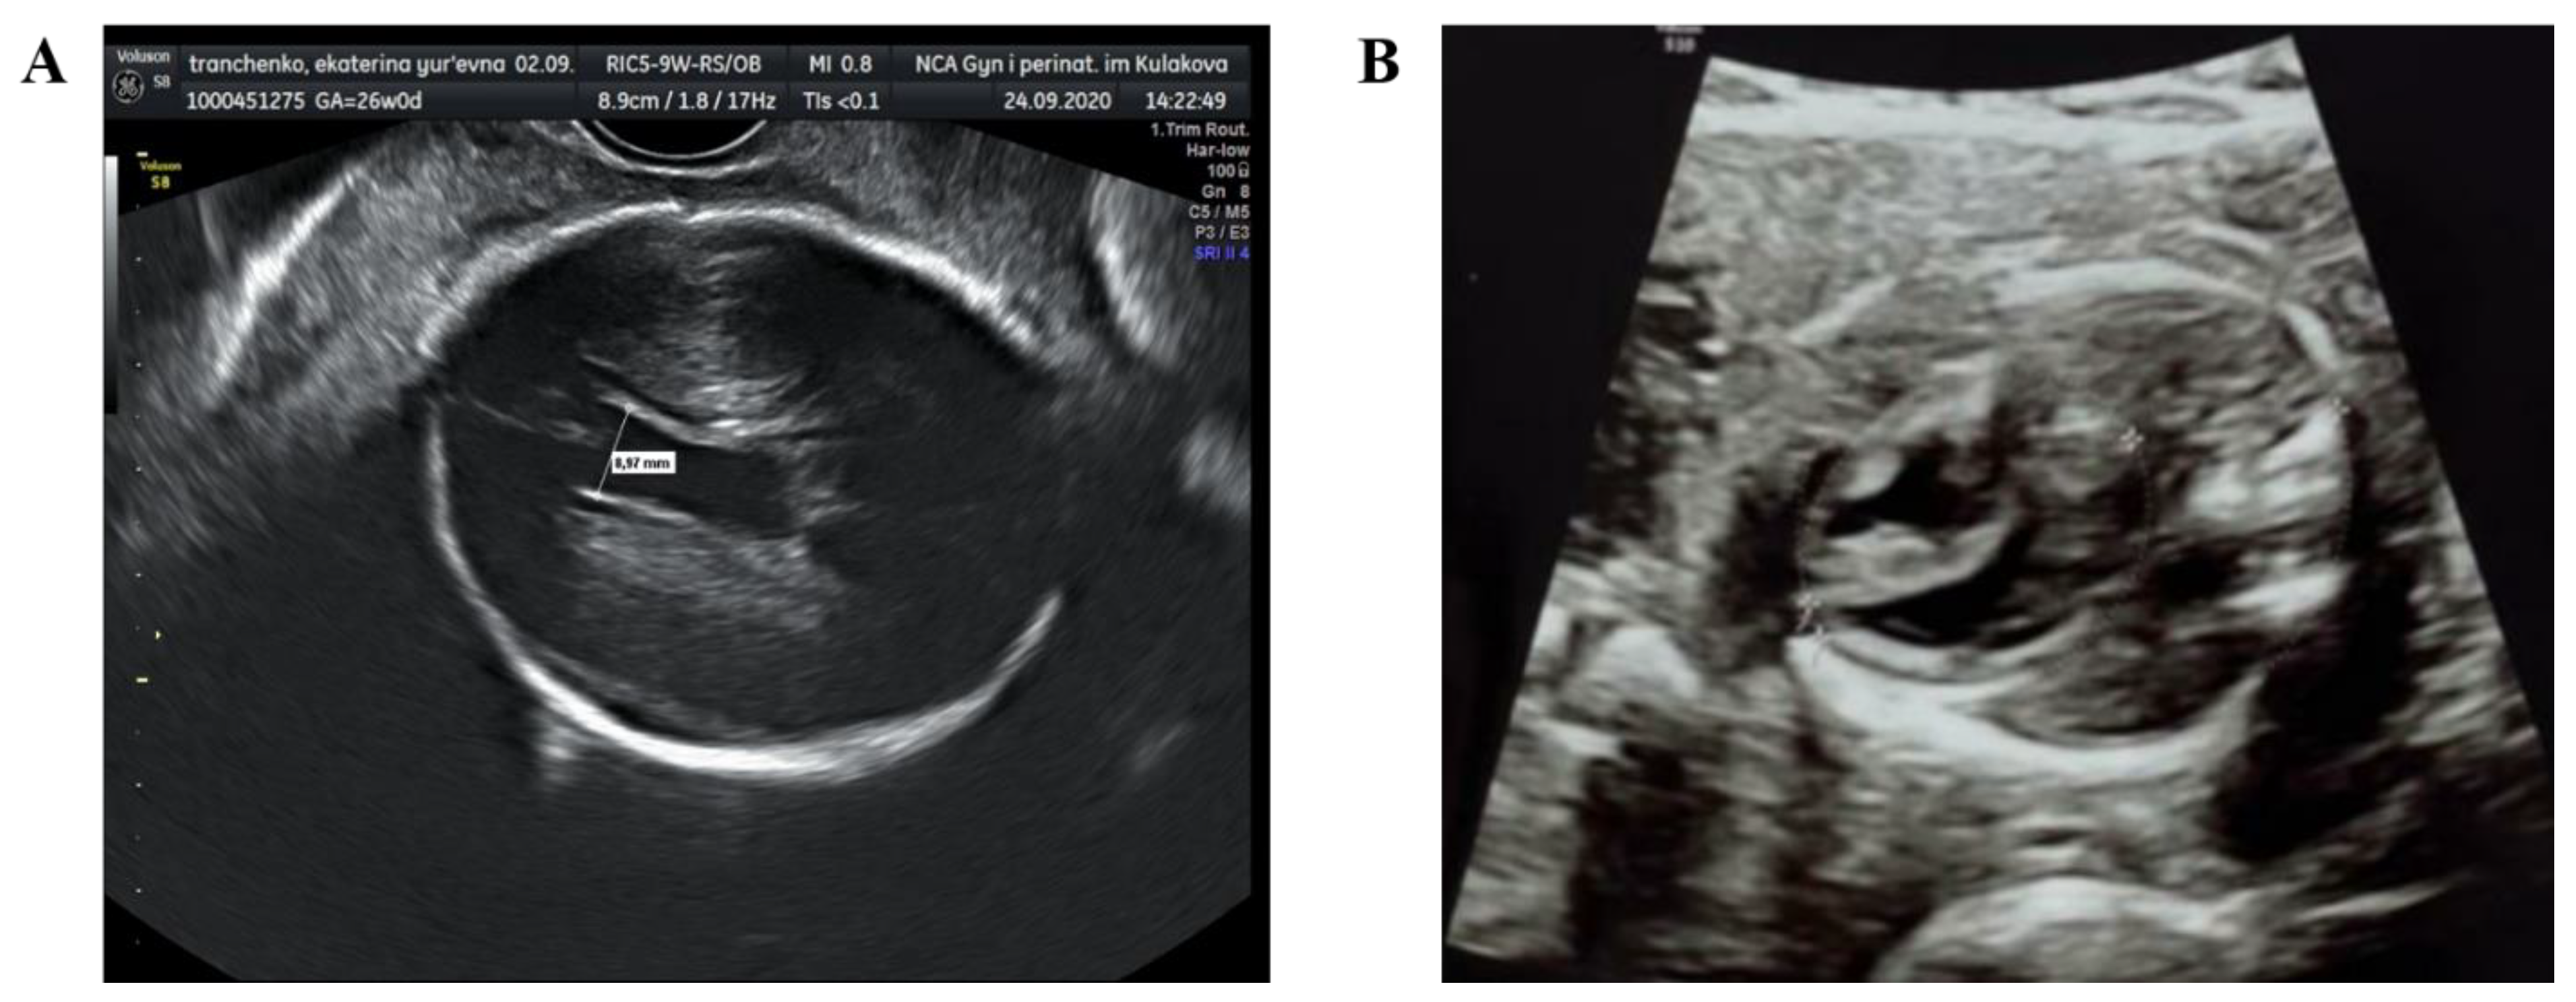

Starting from the 23rd week of gestation, the fetus was regularly monitored. According to the Doppler scan at the 25th week of gestation the impaired feto-placental circulation was observed—fetal umbilical artery Doppler pulsatility index was 1.9, absent end-diastolic flow, middle cerebral artery pulsatility index was 1.3, peak systolic velocity was 40 cm/s, decreased cerebroplacental ratio was 0.68, a-wave in ductus venosus was positive. The uteroplacental circulation was normal. The ultrasound scan showed fetal growth restriction (1st percentile), right ventricular hypertrophy, hydropericardium, decrease in global heart contractility (Figure 1). According to neurosonography, echo-characteristics of hypoxic-ischemic brain injury (leukomalacia in periventricular area), intraventricular hemorrhage (blood clots in lateral ventricles) and partial agenesis of the corpus callosum were found.

Figure 1.

Ultrasound fetal heart scans at the 25th week of gestation: (A) intraventricular hemorrhage; (B) myocardial hypertrophy.